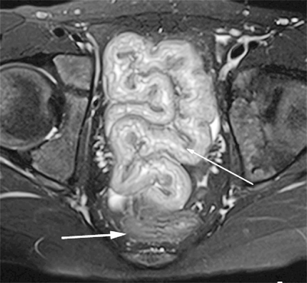

Perianal disease in pediatric Crohn disease: a review of MRI findings

Perianal complications of Crohn disease are a common occurrence in children and can result in significant morbidity when not accurately characterized prior to surgical intervention. MRI is an excellent imaging modality for the evaluation of perianal inflammatory bowel disease – allowing characterization and detailed description of perianal fistulas. MRI has many advantages over other imaging modalities for the pediatric patient. Radiologists will benefit from a sophisticated understanding of perianal anatomy, the classification of perianal fistulas, the advantages MRI offers in characterization of perianal fistulas as well as the common and incidental findings that are important in the MRI evaluation of perianal inflammatory bowel disease in children. Perianal fistulas are found at a high rate in pediatric referrals and are more commonly found in male patients.